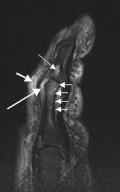

Enthesitis

Enthesitis is inflammation of an enthesis (the site where a tendon or ligament attaches to a bone). In PsA, enthesitis most often occurs at the attachment of the calcaneal tendon (Achilles tendon).[16] It may also occur at the epicondyles of the elbow, plantar fascia, tendon of the quadriceps muscle, patella (knee bone), iliac crest (part of the hip), rotator cuff attachment, or supraspinatus attachment.[1][16][4]

Enthesitis is sometimes considered a hallmark sign of PsA.[16] Sometimes it may appear before any other sign of PsA or be the only sign of the disease.[1] The same person may have multiple sites with enthesitis.[16] Overall, enthesitis occurs in 42% of people with PsA.[16] However, this figure varies significantly from 6% to 72% in reports.[16] Enthesitis in PsA is associated with more active disease and the coexistence of fibromyalgia.[16]

Enthesitis, if present, may cause pain over a wider area around the joint.[17][9] Pain can also occur in and around the feet and ankles, especially if there is enthesitis in the Achilles tendon or plantar fasciitis in the sole of the foot.[7]